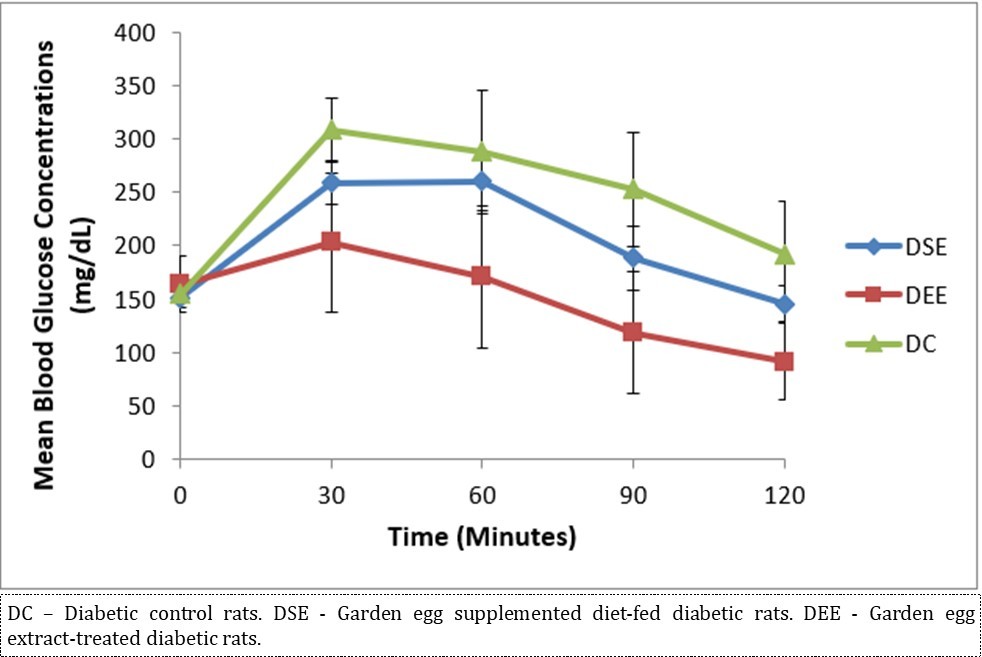

Figure 2 illustrates the effect of S. aethiopicum on glycemic tolerance as assessed by the incremental areas under the glycemic response curves. Garden egg significantly enhanced glycemic tolerance in DSE and DEE rats compared with the controls. The glycemic tolerance effect on DEE rats is comparably better and more improved over that of the DSE rats. The glycemic response to glucose load in all experimental groups peaked at 30 minutes of the 2 hour-duration.

Figure 2.Effect of S. aethiopicum on glycemic tolerance/profile (n = 5/group).

Due to different species of garden egg in nature, likelihood of variation in its effect on weight reduction is expected. There is an uncited claim by some nutritionists that green garden egg species works better for weight loss compared to other species. However, findings obtained in our study using the white species with green stripes (S. aethiopicum L) revealed a remarkable reduction in weight gain in diabetic rats. Though, our present study did not compare species effect on weight gain, in our subsequent research however, we shall conduct a study to correlate species and weight-lowering effect. Meanwhile, based on the present outcome of this study, recommendation of the white-with-green-striped species should be encouraged for beneficial optimal effect on weight reduction. The beneficial impacts of S. aethiopicum on glycemic status and profile are depicted in Table 3 and Figure 2. The mean FBS concentrations decreased significantly (P < 0.05) in both DEE and DSE groups (DEE >> DSE, P = 0.025) compared with the control. The observed difference in their values was similar in manner to its effect on weight gain. The glycemic tolerance improved remarkably in both groups. This antidiabetic potential may be attributed to a major phenolic compound called chlorogenic acid (5-O-caffeoyl-quinic acid; CGA) present in garden egg 13, 21. Bhaskar 13 and Plazas 21 studies revealed that chlorogenic acid possessed anti-obesity, anti-inflammatory, anti-diabetic and, cardio-protective properties. The incremental areas under the glycemic response curves of DEE and DSE rats decreased remarkably compared with the control (Figure 2). The postprandial glycemic response peaked at 30 minutes of glucose challenge in both groups. The TC, TG and LDL-C concentrations decreased significantly with corresponding significant increase in HDL concentration in DEE and DSE rats (Figure 3). However, the extract impacts more beneficial antilipidemic effect than the supplemented diet. This finding also suggests that the optimal antilipidemic effect can be derived when S. aethiopicum is consumed in fresh or raw form than in mixed meal. The antilipaemic effect of eggplants has been attributed to an important phytonutrient compound called anthocyanin found in abundance in the skin of the eggplant which was reported to improve lipid profile through lipid peroxidation and serum antioxidants concentrations increase 27. Besides this antilipaemic activity, anthocyanin has also been reported to play significant role against diabetes, neuronal problems, cardiovascular disorders, and cancer as well 30. The pancreatic tissues sections’ photomicrographs examined under high power magnification (x 400) light microscope revealed the effects of S. aethiopicum on pancreas histoarchitecture. Figure 4 shows the normal appearance of the pancreatic histoarchitecture obtained from a healthy non-diabetic Wistar rat. Comparison of the experimental grouped rats photomicrographs with the normal revealed that the histoarchitecture of the pancreas in DEE and DSE (Figure 5, Figure 6) rats were preserved with no visible pathologic changes while the photomicrograph of the pancreas from diabetic control (DC) rats (Figure 7) shows distorted Islet margin with lymphocytic cells infiltration and moderate necrotic parenchyma. Examining the histological consequence of any product prior to recommendation is very essential because histological analysis of target organs for pathological changes surveillance is necessary to enhance screening assessment of quality and safety of product prior to recommendation for human consumption 31